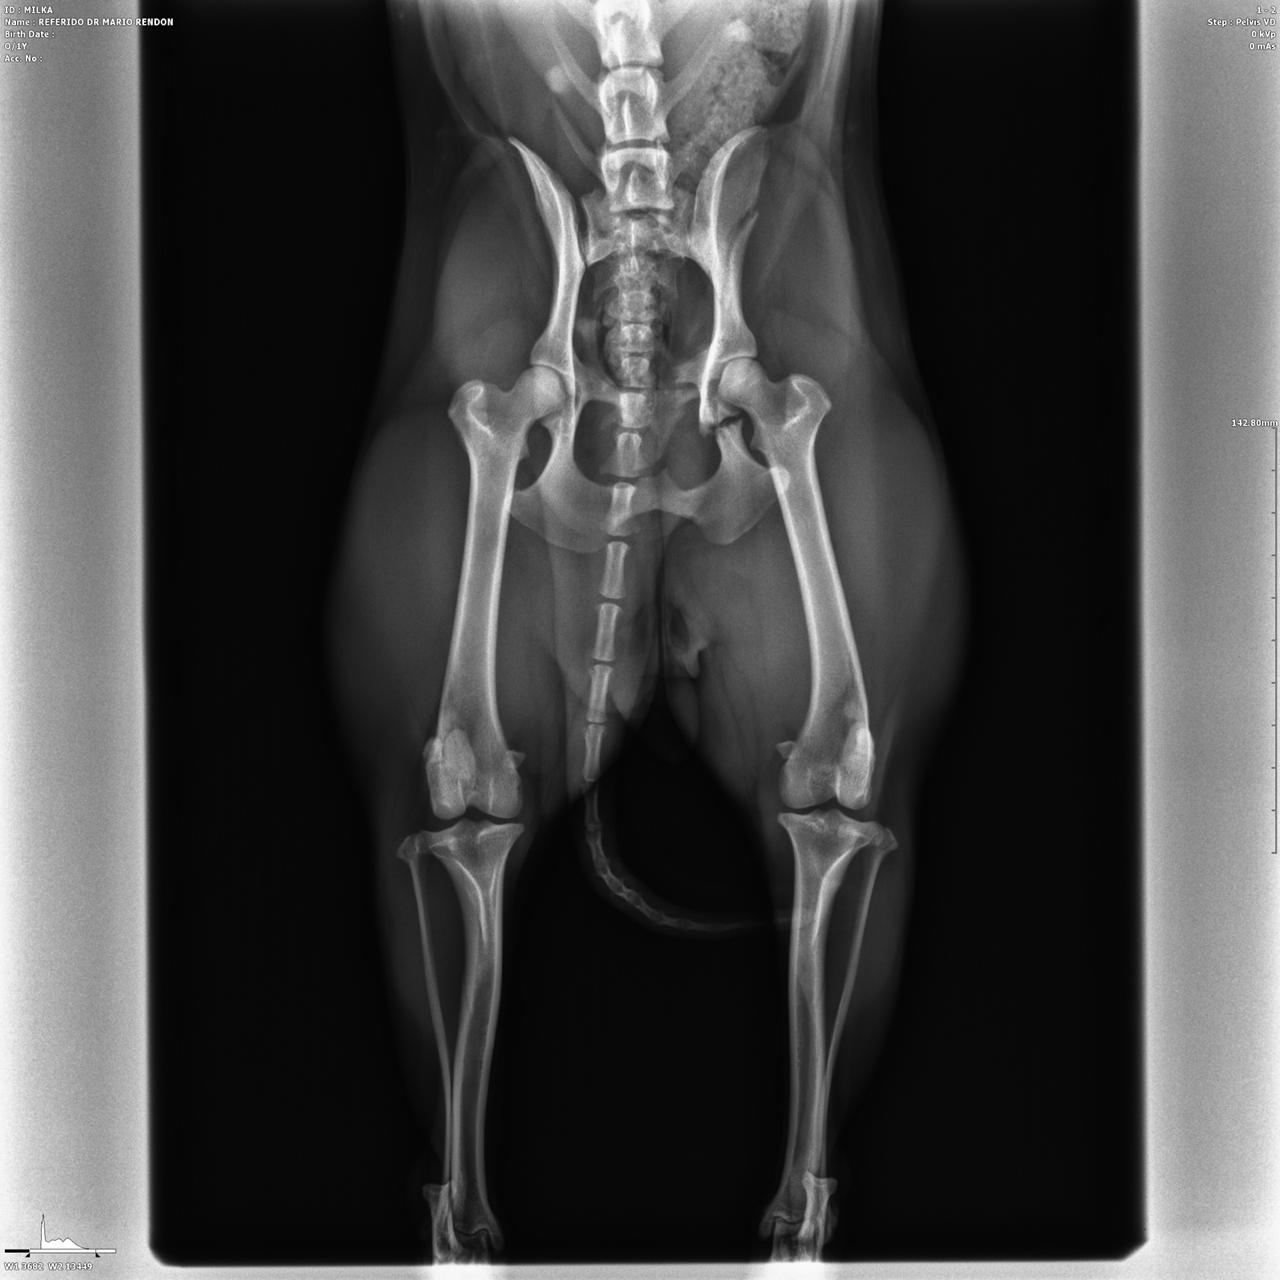

El Doctor Matias Montilla MP 163 especialista Traumatologo y ortopedista un ejemplo de lo que es brindarle importancia y seriedad a la medicina de animales de compañía y nos cuenta que en su clínica situada en capital (Mendoza 1771 norte ) incorporaron hace poco tiempo un maquina de última tecnología en radiología digital que es indispensable para el rápido diagnóstico en fracturas , malformaciones óseas, enfermedades Oncologicas óseas, y enfermedades articulares degenerativas, todas ellas son dolencias que cualquier mascota podría sufrir y podrías no saberlo.

El doctor nos explicó lo importante que es el rápido diagnóstico mediante Imagenes claras y revelado inmediato, este detalle puede salvarle la vida a tu mascota y evitar el sufrimiento. Por esto su visión de invertir en tecnología y educación continúa son sus principales objetivos.